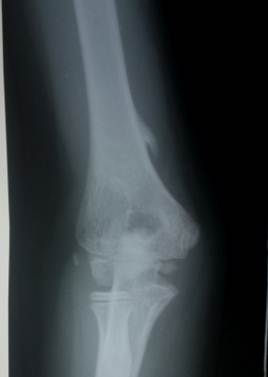

Костно

– хрящевой экзостоз, случайно обнаруженный у мальчика 13 лет на рентгенограмме

локтевого сустава. Снимок выполнен по поводу травмы - обратите внимане на

небольшое смещение ядра окостенения латерального надмыщелка. Была предпринята иммобилизация конечности на

10 дней. Экзостозы в нижней части плечевой кости часто имеют форму акульего

плавника, это типично для них. Отчётливо виден перелом экзостоза. У больного не было никаких его клиинческих

проявлений. Рекомендована контрольная рентгенограмма области экзостоза в 15

лет. Вероятно, что удалять его не потребуется. А если бы не лёгкая травма, то

об экзостозе вообще никто не узнал бы.